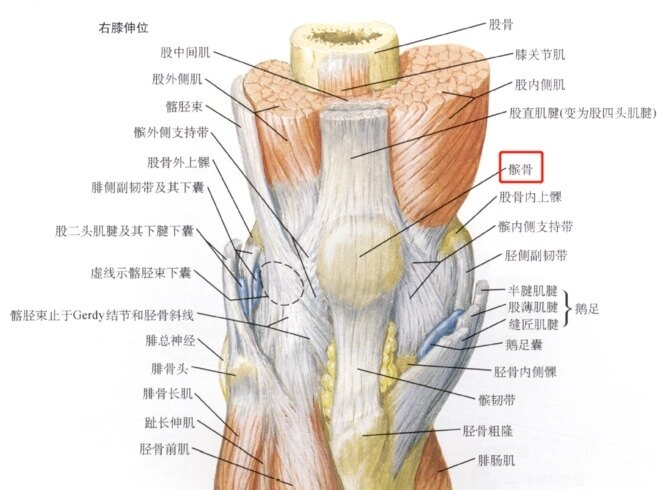

股骨、胫骨、腓骨、髌骨共同构成膝关节的骨结构。在膝关节前方游离,扁栗状,神一般存在的那个就是髌骨。北方称膝盖骨或波棱盖。还有人称其为迎面骨。医学上它是人体最大的一颗籽骨。

髌骨和股骨滑车是天衣无缝的匹配的,正常的髌骨,在滑车上,不偏内也不偏外。可人的生长发育那可能都那么完美呢?人们都是或多或少的存在些发育上不足。对于髌骨,时常偏外,就是常见的髌骨半脱位类型。